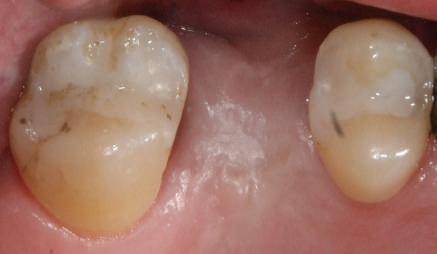

Şapte luni mai târziu (fig. 2), acele bonturi individualizate din prima etapă au manifestat semne de recesie de 1-3mm. Atitudine: S-a decis reprepararea intraorală a tuturor bonturilor (fig. 3), astfel încât toate marginile bonturilor să fie la nivelul sau sub marginea gingivală (de notat că 1.1. şi 2.1. au fost submersaţi ulterior pentru a avea sprijin implantar deplin).

Deşi reprepararea a îmbunătăţit marcat estetica finală, a necesitat aplicarea şnurului de retracţie, amprente noi şi turnări noi.

Un caz separat dar similar ilustrează în figurile 4 și 5 reprepararea intraorală a bontului.

Cazul (1): Reprepararea intraorală a bonturilor Figurile

1. Aspect după inserarea primului set de bonturi implantare individualizate.

2. După 7 luni, bonturile individualizate din prima etapă au prezentat recesie de 1-3mm.

3. Bonturile repreparate intraoral.

Alt caz (1) Figurile

4. După osteointegrarea implantului 2.4., s-a observat recesia în etapa de amprentare a implantului 2.5.; s-a decis reprepararea marginilor bontului individualizat CAD/CAM 2.4. Înainte de preparare s-a aplicat şnur de retracţie pentru a evita lezarea ţesutului şi a îmbunătăţi vizibilitatea dintelui 2.3. şi a marginii bontului implantar individualizat. Aşa cum era de aşteptat, recesia a fost mai mare de-a lungul versantului distal al bontului 2.4. adiacent locului de extracţie vindecat/cu implantul mai nou.

5. Bontul individualizat aplicat (2.5.) cu bontul repreparat anterior (2.4.). Nu a survenit recesie nouă de o perioadă de peste 3 ani.